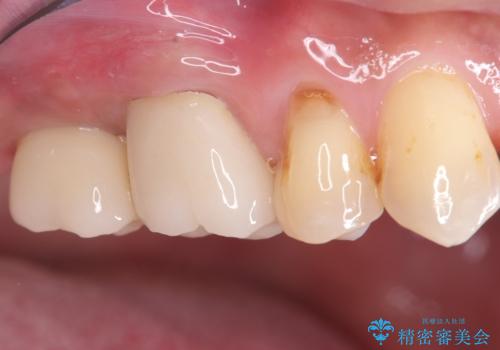

まず、右上6・右下6の根管治療を再度行い、根の状態をしっかり整えた上で、セラミッククラウンを装着しました。さらに、欠損していた右上7・右下7にはインプラントを埋入し、セラミッククラウンを装着。治療後は、「奥歯でしっかり噛めるようになり、不安なく食事ができるようになった」と患者様にも大変ご満足いただきました。